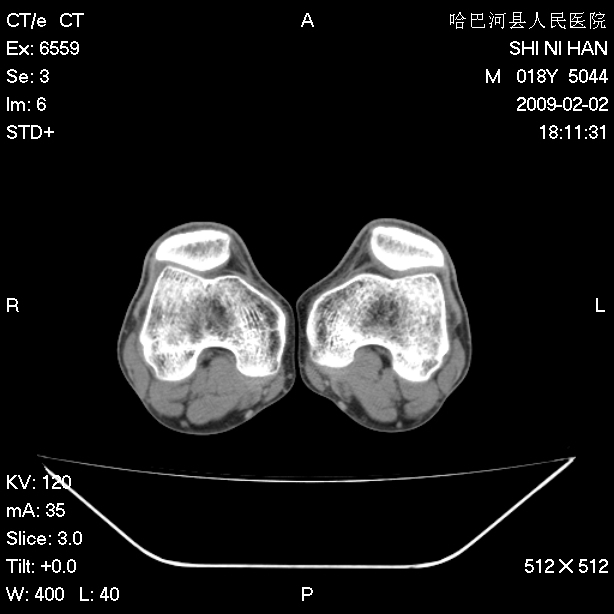

标题: CT17889:外伤后右膝关节反复疼痛3年余 [打印本页]

标题: CT17889:外伤后右膝关节反复疼痛3年余

mri检查,看看半月板情况如何。

可能韧带有问题!

ct未见明显异常。关节腔未见明显积液,半月板未见明显撕裂。但最好还是mri看看韧带及半月板情况。